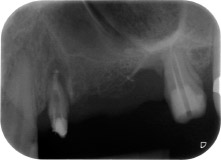

Fig. 1: 58-year-old patient. Preoperative radiograph showing an apical periodontal lesion at tooth 24 and horizontal loss of alveolar bone in the second quadrant.

A 58-year-old female patient complained of pain and increased mobility of her bridge abutment tooth 24. Periodontal inflammation was present with pocket depths of 7 mm mesiobuccally and more than 12 mm distally, as well as third-degree furcation involvement. Moreover, the radiograph revealed an extensive periodontal lesion around the apical region of the (alio loco) endodontically pretreated tooth 24 (Fig. 1).

One month later, on the day of surgery, pain and inflammation at tooth 24 were minimal, but mobility of Miller class 2 was still present. After opening the flaps and cleaning the periapical and peri radicular infected tissue, the extent of the bone defect became obvious (Figs. 2 and 3).

At the buccal root, all vestibular and distal bone was missing. Attachment was essentially restricted to the palatal root, underlining the preliminary poor prognosis. Tooth 27 also showed a reduced horizontal attachment and a minimal apical rarefaction (cf. Fig. 1) without clinical symptoms.

total loss of bone and attachment

Fig. 2 and 3: After raising flaps, one month after endodontic revision and initiation of full-mouth periodontal therapy, the buccal root of tooth 24 showed a total loss of bone and attachment.